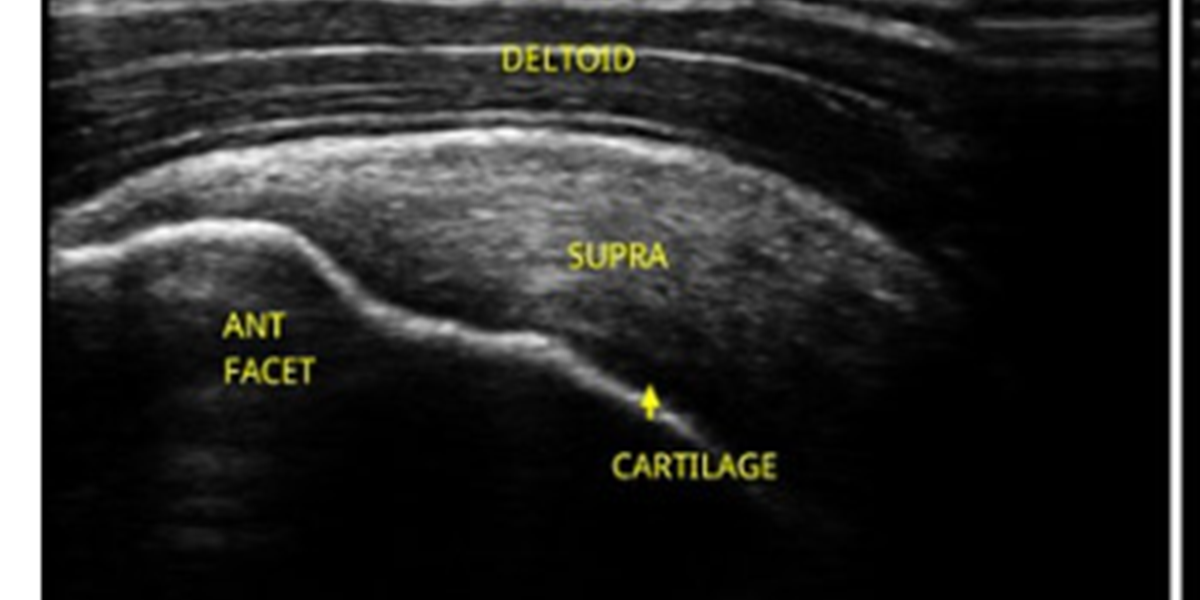

A thorough, virtual, mentoring course which enables you to build on your anatomical knowledge and sonography skills week by week, joint by joint.

Each module will include three or four weekly sessions covering the ultrasonography of an anatomical area in detail, giving you time to practice in between. The sessions will include pre-recorded practical demonstrations and detailed instruction - you can scan while you watch, improving your skills and confidence.